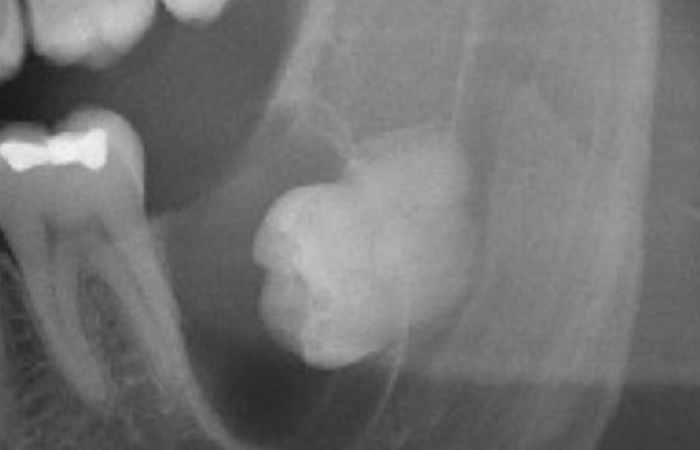

الأكياس سنية المنشأ – خيارات العلاج والمضاعفات

الأكياس سنّية المنشأ – الأنواع، التشخيص والأسباب